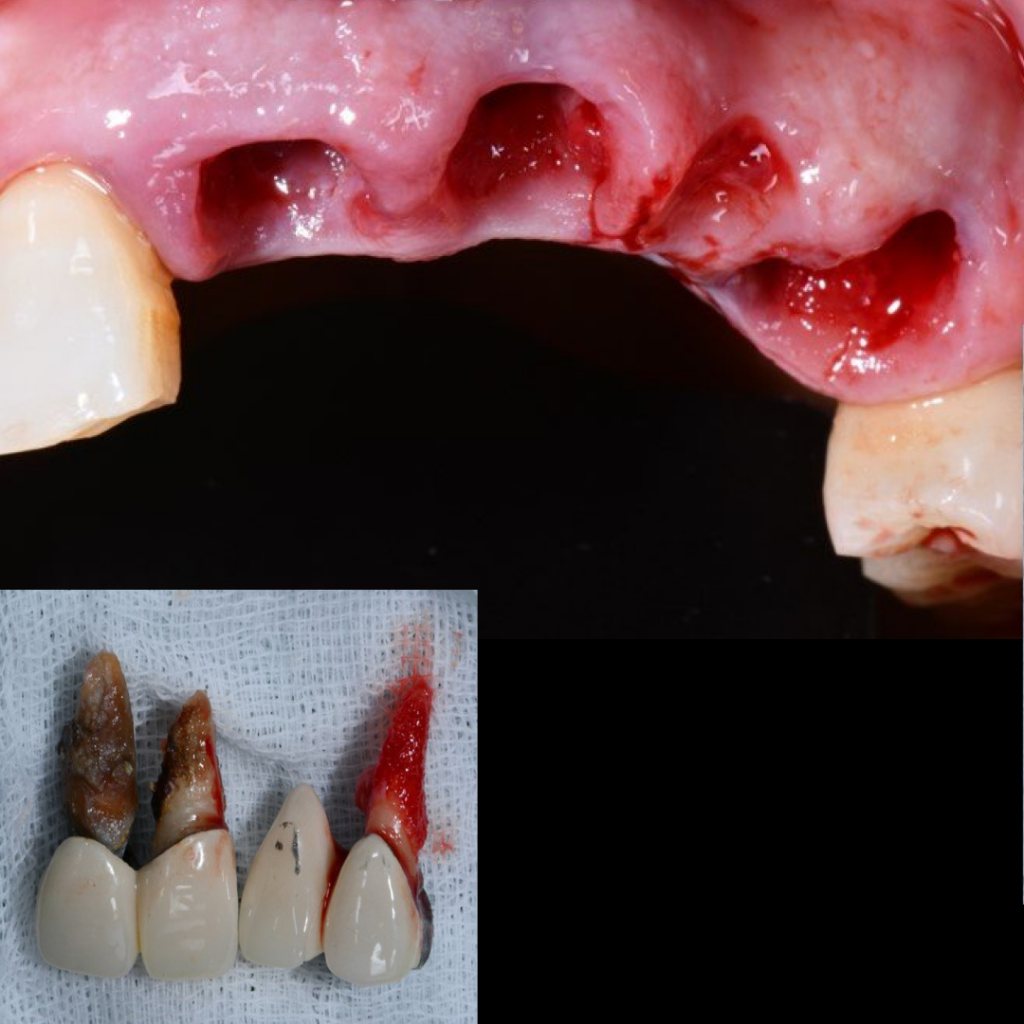

- Удаление несъемного мостовидного протеза по причине подвижности во фронтальной области верхней челюсти с диагнозом "Хронический генерализованный парадонтит и множественный кариес"

- Проведение имплантации AnyRidge с немедленной нагрузкой